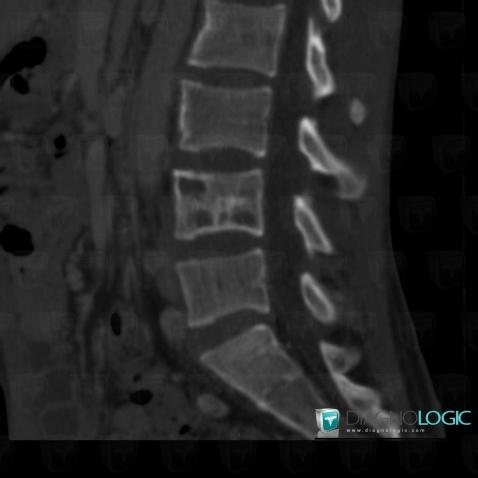

Tuberculosis, Vertebral body / Disk, Theoretical

Here is the specific information in the key image above:

- Diagnosis Tuberculosis (link to Osteomyelitis), Location(s) Vertebral body / Disk, with gamuts Vertebral fracture and vertebra plana

- Diagnosis Tuberculosis (link to Osteomyelitis), Location(s) Vertebral body / Disk, with gamuts Discal / Intraverbetral gaz